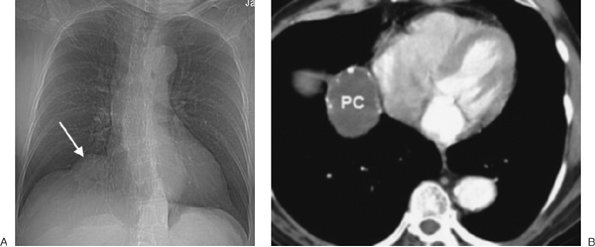

FIGURE 6-33. Pericardial cyst. A: PA chest radiograph shows a round opacity (arrow) at the right cardiophrenic angle. B: CT scan shows the mass (PC) to be of homogeneous fluid attenuation with rim calcification.

The imaging features of esophageal duplication cysts may be identical to those seen with bronchogenic cysts, except that an esophageal duplication cyst will always have a peri-esophageal location (Fig. 6-32). Neurenteric cysts are posterior mediastinal cystic lesions connected to the meninges through a midline defect in one or more vertebral bodies. Associated vertebral anomalies suggest the diagnosis. Pericardial cysts arise most frequently in the right cardiophrenic angle as a result of anomalous outpouching of the parietal pericardium. The cysts typically contact the heart, diaphragm, and anterior chest wall (Fig. 6-33). The majority are sharply marginated, somewhat triangular, and of near-water attenuation on CT scans (Fig. 6-34).